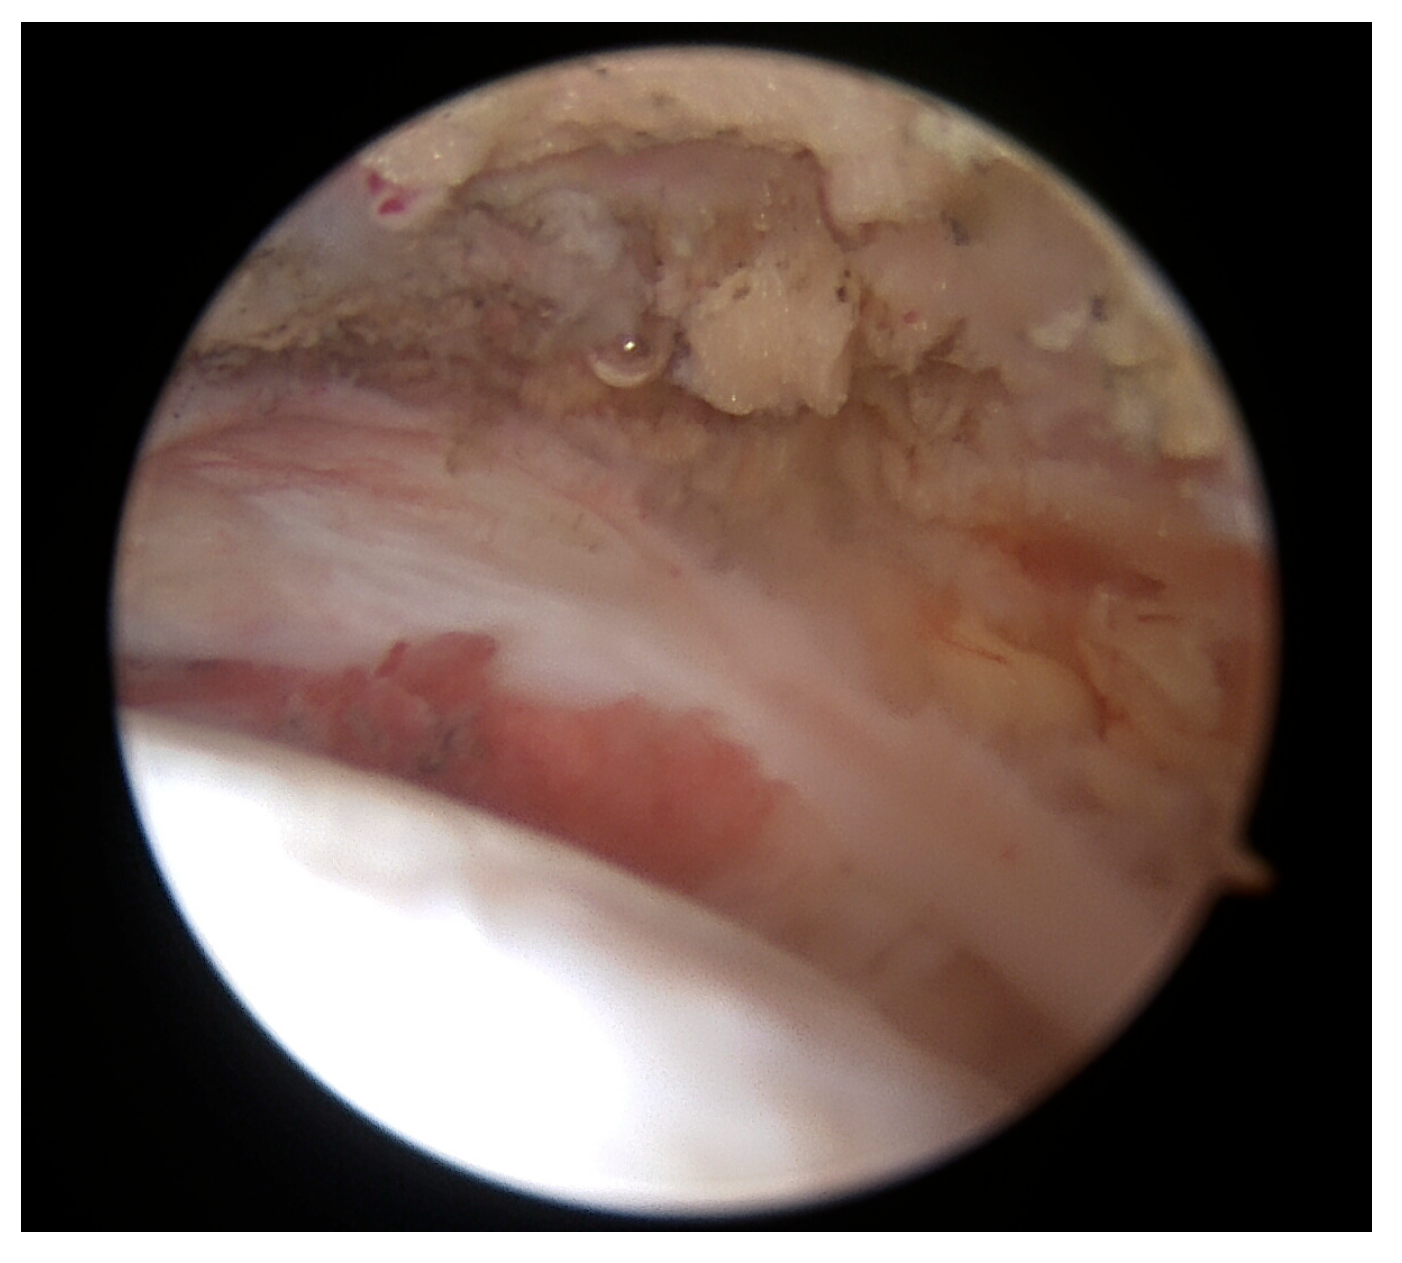

To complete the procedure, acromioplasty was performed via lateral and posterior portals, with the extent of resection standardized using an acromizer shaver blade 5.0 (Arthrex, Munich, Germany). At the end of the reconstruction and acromioplasty, the reconstruction site was dried out in order to prevent migration of the augmenting tissue. Once the subacromial space was dried, the PRP–bursal tissue mixture was applied all over the reconstruction site (Figure 4a–c) through one of the lateral portals using the applicator under direct arthroscopic visualization through the posterolateral portal and the wounds were closed. The remaining PRP was injected intra-articularly before covering the incisions.

Figure 4.

(a) Application of PRP–bursal tissue mixture all over the reconstruction site through one of the lateral portals (b) using the applicator under direct arthroscopic visualization (c) through the posterolateral portal.